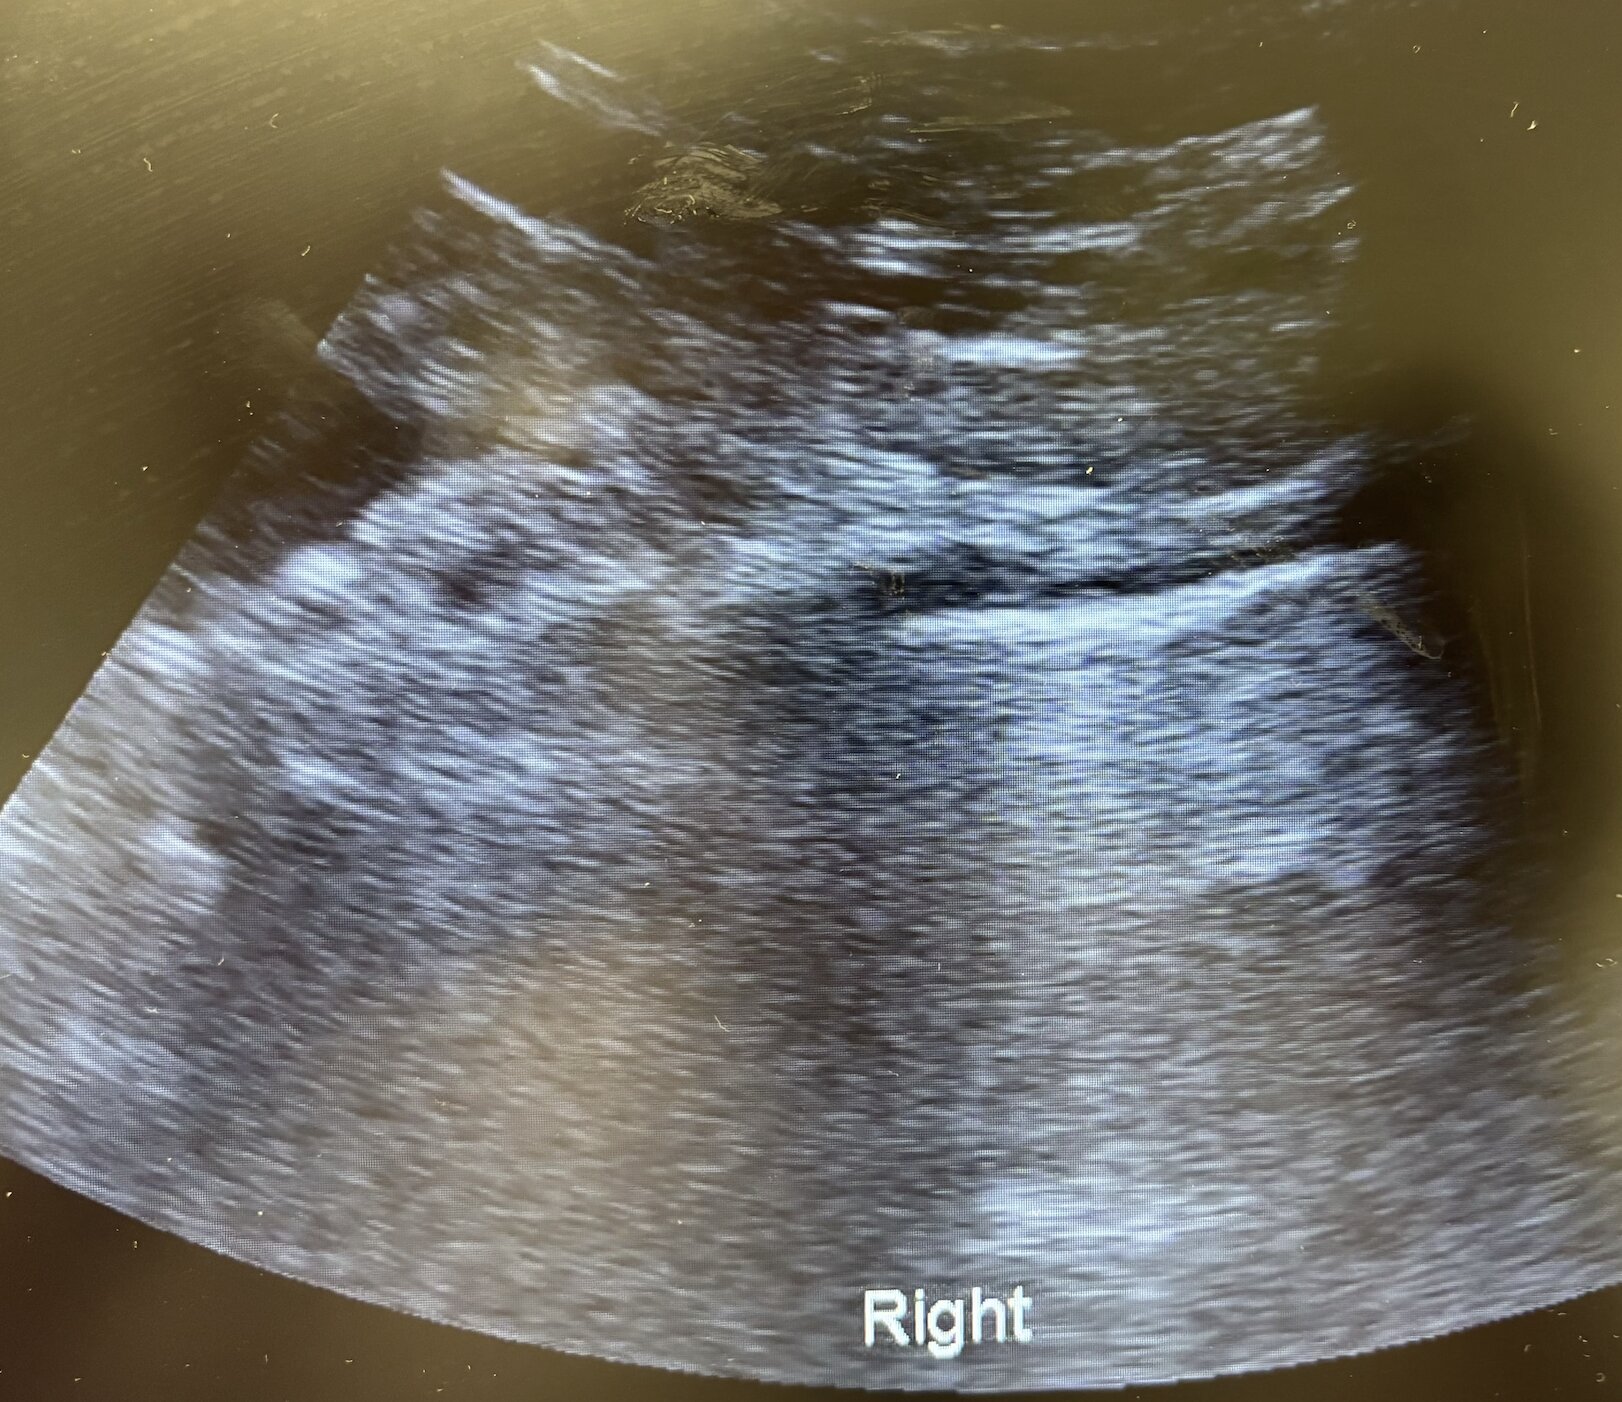

Antes de solicitar otras pruebas complementarias, se decide realizar ecografía clínica pulmonar. Se detecta un patrón intersticial focal en base izquierda, con condensación basal, mínimo derrame pleural y líneas B periféricas. Deslizamiento pleural conservado bilateral.

Como curiosidad, las neumonías suelen presentarse como área hiperecoicas o con sombras acústicas en casos más graves.